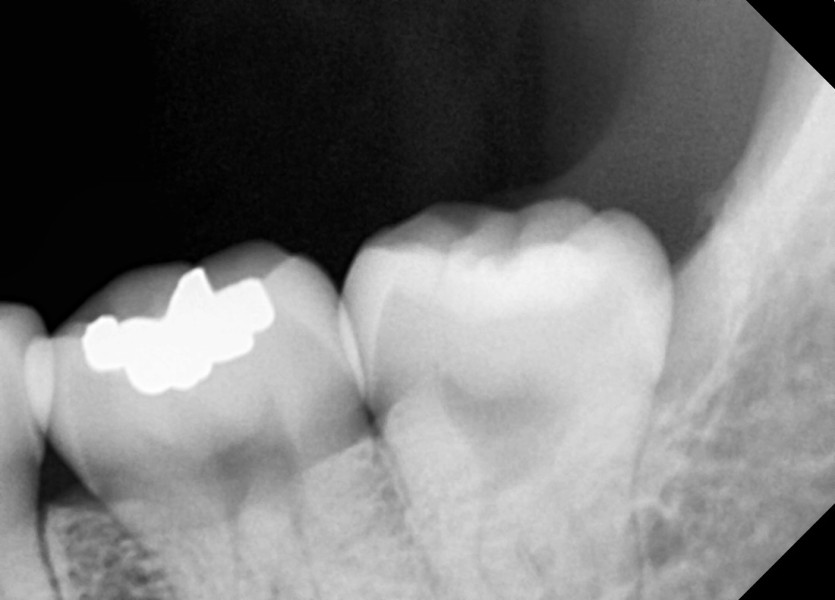

#38,48 사랑니 발치

구강 외과 전문의가 당일 발치했습니다.